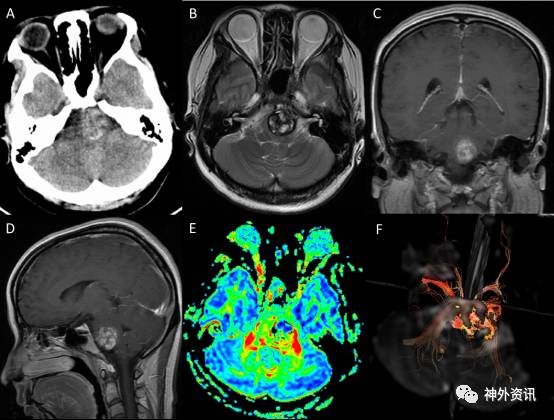

患者:28岁,因“右侧肢体麻木乏力伴行走不稳及复视1月余”入院。患者1月前无明显诱因下出现右侧肢体麻木乏力,伴行走不稳,诉有复视,遂往当地医院就诊,查MRI考虑脑干海绵状血管瘤。近来上述症状加重,再次行MRI检查,示脑干出血范围较前增大(图1)。为求进一步诊治,门诊以“脑干海绵状血管瘤”收住入院。

图1. 术前影像学检查:A)头颅CT示脑干团片状混杂高密度影,提示出血;B)T2加权轴位上脑干见团片状混杂信号影,靠近腹侧面,最大直径约23mm,周围见含铁血黄素环;C)增强后冠状位和D)矢状位未见明显强化;E)和F)弥散张量成像(DTI)显示左侧皮质脊髓束受压向外侧推移,部分缺损。